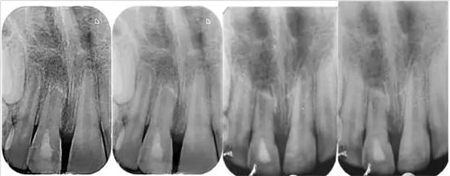

影像學檢查:根尖片以及全景片(圖2)提示牙槽骨骨折,根尖挫入至唇側骨板或鼻底。根尖片提示牙11,12 和21根尖發(fā)育不完全,呈喇叭口狀。受累牙的根管壁薄且不完全成形(圖2)。牙片顯示沒有冠折和根折。

( 圖2)

隨訪12個月的X線記錄顯示:在年輕恒切牙的根管壁上有硬組織沉積。從長度上看,牙根并沒有繼續(xù)發(fā)育,但根尖處硬組織沉積,而且?guī)缀蹰]合了(圖 8)。